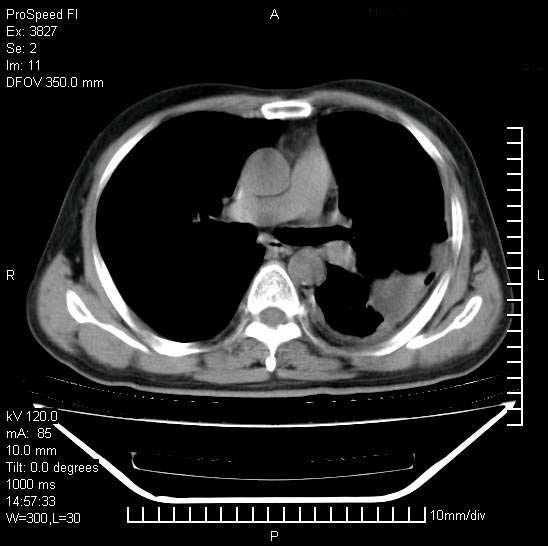

男性,一月前出现右侧肋区疼痛,较剧烈,干咳,无发热,自诉使用抗炎药后缓解,几天前又出现左侧剧烈疼痛,

发热,体温38。9,今天ct,考虑左侧包裹性脓胸,胸腔积液,右上中肺小斑片影,结核/炎症?胸水未见恶性细胞。

左侧肺脓疡,化脓性胸膜炎(脓胸),不支持结核诊断,建议继续抗感染治疗

支持左侧肺脓肿并脓胸,肺内炎症,建议继续抗炎治疗后复查。

脓胸没问题,肺内还可见感染灶,感觉不像是结核性病变.